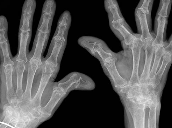

2. 류마티스 관절염

류마티스 관절염은 손가락 마디 통증을 유발하는 대표적인 자가면역 질환으로, 몸의 면역체계가 스스로의 관절을 공격하여 염증을 유발하는 것이 특징입니다. 특히 여성에게서 많이 나타나며, 방치할 경우 관절이 변형되거나 기능 장애가 생길 수 있어 주의가 필요합니다.

증상

- 좌우 대칭적인 관절 통증과 부종

- 아침에 심한 관절 경직(30분 이상 지속)

- 피로, 미열 등 전신 증상 동반